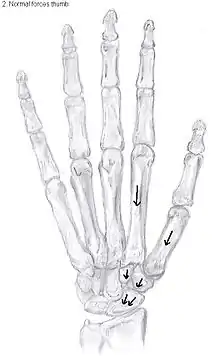

The large forces, which the CMC1 joint has to withstand, are considered to be another cause of CMC OA.[12] During daily manual activities, such as grabbing and pinching, the thumb is constantly being used. The forces generated by these movements have an enlarged impact on the CMC1 joint because of the leverage within the thumb. This makes the joint even more sensitive to wear and tear.[12]

This high mobility is due to the little intrinsic osseous stability of the joint. This causes the CMC1 joint to be more unstable compared to the CMC joints of the other fingers.[18] Because of this instability, the joint is more susceptible to be damaged.[12] To remain stable the CMC1 joint has to rely on the surrounding ligaments for support. These ligaments provide the ability to subject high pressure loads, particularly during pinch and grasp manoeuvres.[19]

16 ligaments surrounding the CMC1 joint are identified, which give strength and stability to the joint. Of these ligaments, the deep anterior oblique ligament, also known as the palmar beak ligament, is considered to be the most important stabilizing ligament.[20]